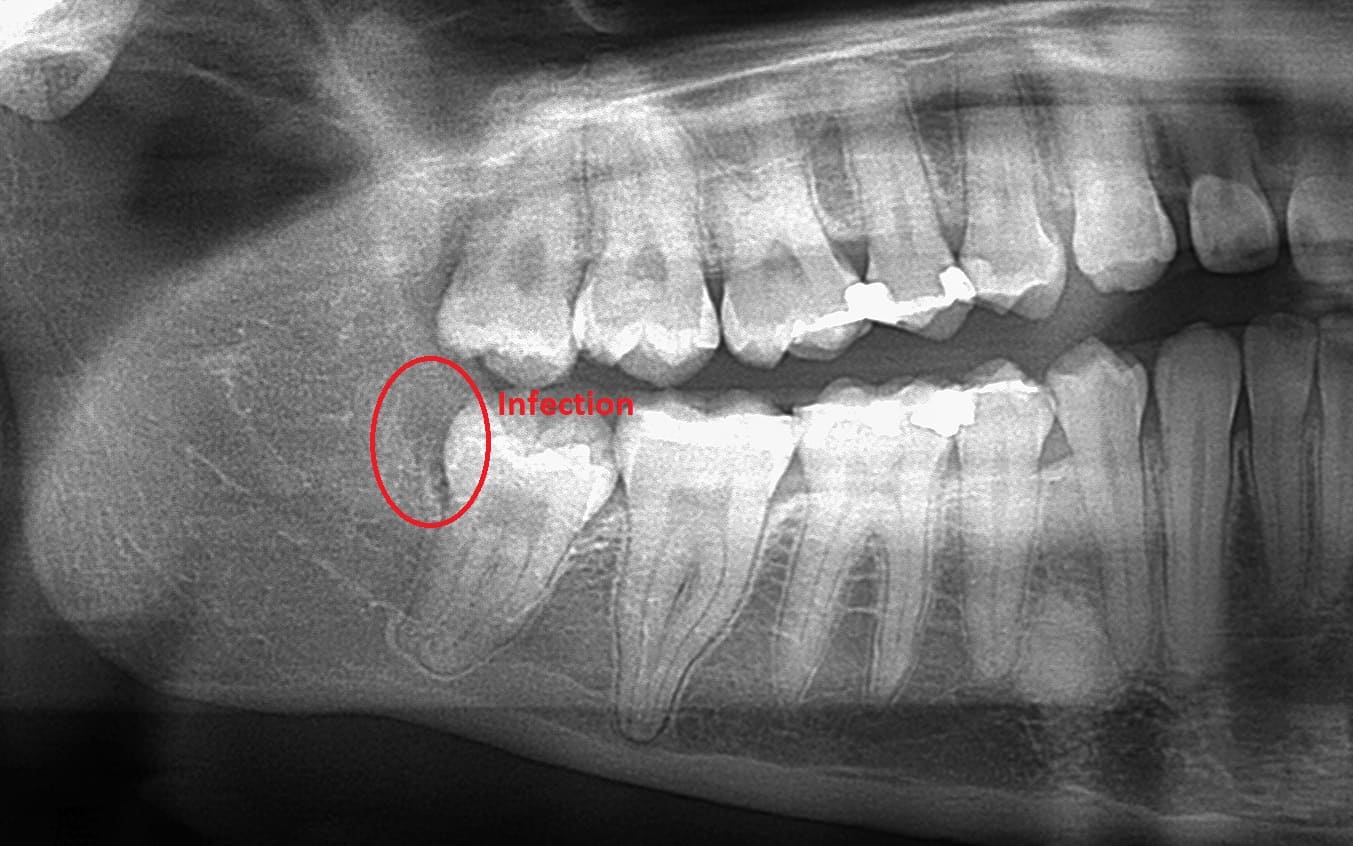

Dental X-rays are more than just tools for diagnosing cavities; they provide a comprehensive view of your oral health status. By allowing dentists to detect problems before they become severe, these images can save patients time, money, and discomfort in the long run. Early detection through modern imaging technology can reveal hidden decay between teeth, bone loss due to gum disease, or even cysts and tumors that are not visible during a standard exam.

- Tumors - Spotting abnormal growths or cysts within the jawbone.

- Bone Loss - Evaluating the extent of bone loss associated with osteoporosis or other conditions.

Despite the myths surrounding dental x-rays, they play an integral role in preventative dentistry. X-rays allow dentists to detect issues that are not visible during a standard oral exam. This includes early signs of decay between teeth, problems below the gum line, and changes in bone density that could indicate periodontal disease. By identifying these problems early, fundamental dental treatments can be administered promptly, saving patients from more extensive and costly procedures down the line.